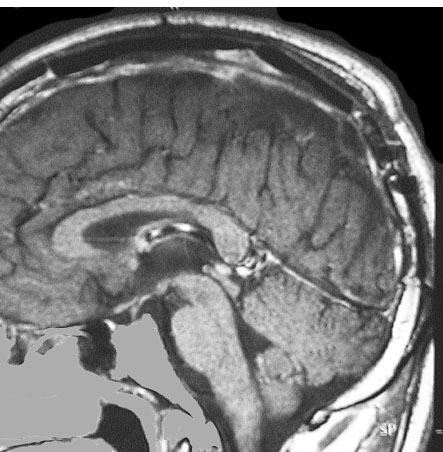

上矢状洞髄膜腫 superior sagittal sinus meningioma

上矢状洞を埋め尽くすように増大して,頭蓋骨浸潤が著しい髄膜腫ですが,ごく軽度の右足脱力以外に何の症状もありません。上矢状洞はゆっくり閉塞すれば,このような頭頂部から後頭部にわたる広範閉塞でも,静脈還流に障害がない場合が多いといえます。大脳の前半部の血流は前頭葉表面の皮質静脈から海綿静脈洞に側副路を形成しています。頭蓋内圧亢進所見もなく,これらはこの髄膜腫がゆっくり増大したということを示唆しています。

手術直後の画像です。全部いっぺんに摘出するのは無理なので,まず前から80%くらいの腫瘍を摘出しました。肥厚した骨はチタンプレートで置き換えてあります。後頭部の上矢状洞内と大脳鎌に少し残りましたが,この6ヶ月後に2回目の開頭術をして全摘出しました。結果的にこの例では,上矢状洞を冠状縫合のあたりから,静脈洞交会まで壁ごと全部摘出しましたが,脳浮腫も何も生じませんでした。腫瘍の両側にある皮質静脈 cortical veinsを損傷しないことが肝要です。

右の病理像は,頭蓋骨浸潤している部分 ですが,骨破壊は良性髄膜腫に特徴的な骨内浸潤像です。この骨浸潤像は悪性像とはいえません。MIB-1は高いところで8%、低いところで3%程度です。